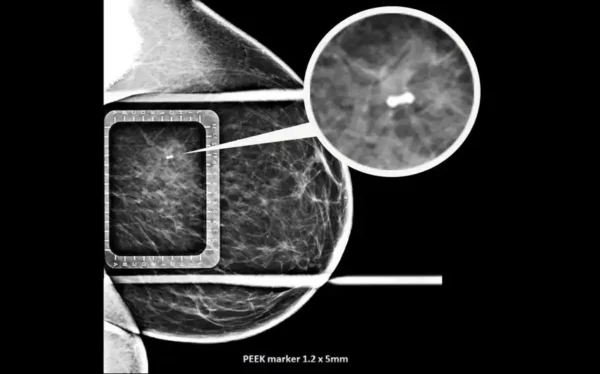

Naviko žymėjimo adata – tai specializuota medicininė adata, skirta tiksliai lokalizuoti navikus prieš chirurgines procedūras ar spindulinę terapiją. Procedūros metu į naviko audinį implantuojamas markeris (auksinis arba PEEK), kuris veikia kaip radiologinis orientyras. Šis sprendimas leidžia gydytojams tiksliai nustatyti naviko vietą įvairių vaizdinimo metodų metu ir užtikrina maksimalų gydymo tikslumą. Markeriai pasižymi puikiu matomumu rentgeno, KT, MRT ir ultragarso tyrimuose.